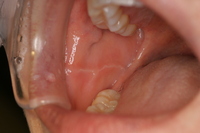

症例です。

両側の頬粘膜です。

白っぽいスジのようなものが確認できると思います。

これは歯の跡が粘膜についてしまったために起こるもので心配ありません。

夜間のくいしばりが強いと口の中の陰圧が強くなり跡がついてしまうことがあります。